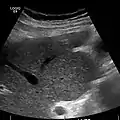

Ultrasound is routinely used in the evaluation of cirrhosis. It may show a small and nodular liver in advanced cirrhosis along with increased echogenicity with irregular appearing areas. Other liver findings suggestive of cirrhosis in imaging are an enlarged caudate lobe, widening of the fissures and enlargement of the spleen. An enlarged spleen (splenomegaly), which normally measures less than 11–12 cm in adults, can be seen and may suggest underlying portal hypertension. Ultrasound may also screen for hepatocellular carcinoma, portal hypertension, and Budd-Chiari syndrome (by assessing flow in the hepatic vein). An increased portal vein pulsatility is an indicator of cirrhosis, but may also be caused by an increased right atrial pressure.[33] Portal vein pulsatility can be quantified by pulsatility indices (PI), where an index above a certain cutoff indicates pathology:

Liver cirrhosis with ascites

caudate lobe hypertrophy in ultrasound due to cirrhosis